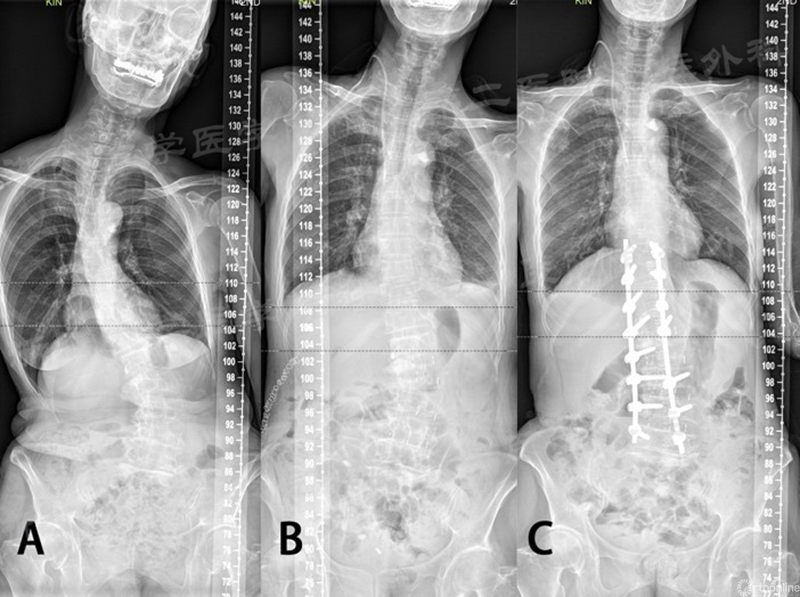

近期该团队对退行性脊柱侧凸患者手术的研究结果表明:采用CLIF技术结合II期再次评估,能获得良好的脊柱的矢状面和冠状面矫正,并为缩短侧凸患者的固定节段奠定基础。初期的临床结果显示,部分患者能有效地减少手术固定节段,这为减少手术创伤,减少手术并发症且保留腰椎的活动度提供了良好的保障,值得进一步的研究。

A.手术前;B.I期CLIF手术后;C.II期后路固定术后